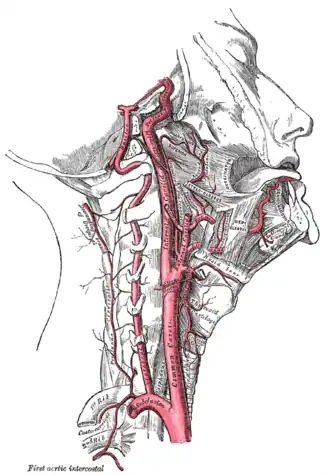

The common carotid artery is the large vertical artery in red. The blood supply to the carotid artery starts at the arch of the aorta (bottom). The carotid artery divides into the internal carotid artery and the external carotid artery. The internal carotid artery supplies the brain. Plaque often builds up at that division, and causes a narrowing (stenosis). Pieces of plaque can break off and block the small arteries above in the brain, which causes a stroke. Plaque can also build up at the origin of the carotid artery at the aorta.